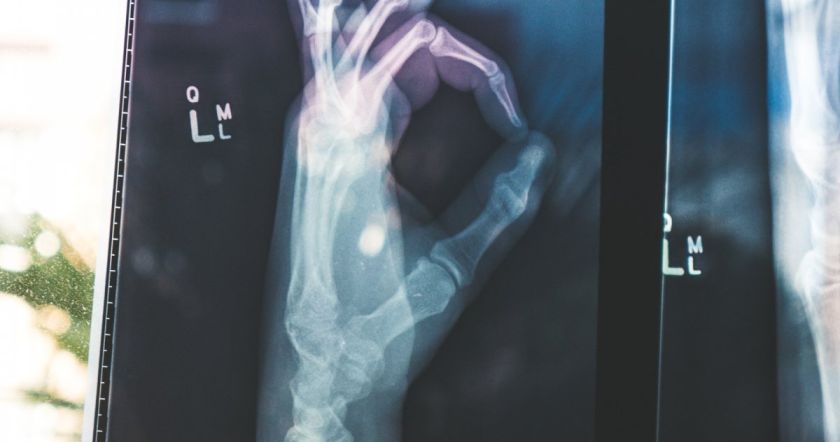

Крепкие кости – это то, что позволяет вам держаться на ногах и стоять прямо. Вместе с мышцами кости поддерживают свободу движений. Здоровые кости также защищают жизненно важные органы и служат хранилищем важных минералов, таких как кальций и магний.

Независимо от вашего возраста, важно поддерживать крепкие и здоровые кости, чтобы сохранить подвижность и снизить риск переломов. С возрастом ваши кости естественным образом становятся слабее в результате потери тестостерона, если вы мужчина, или потери эстрогена, если вы женщина. Снижение этих гормонов приводит к потере плотности костей, что увеличивает риск переломов.

Укрепление здоровья костей — одно из многих преимуществ регулярных физических упражнений. Упражнения оказывают на кости такое же воздействие, как и на мышцы, то есть делают их сильнее.

"Поскольку кость также является живой тканью, она способна реагировать на внешние силы и адаптироваться к внешнему давлению. Таким образом, когда вы регулярно тренируетесь, ваши кости реагируют на это, создавая больше костей, чтобы они могли лучше поддерживать ваше тело во время физической активности. В результате они становятся плотнее и сильнее".